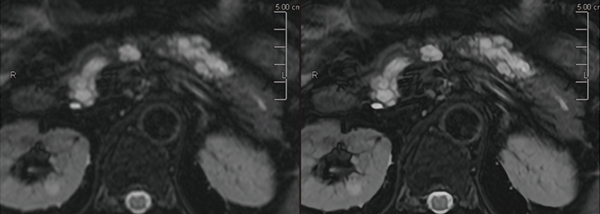

前田医師は、Vantage Centurianで撮像した転移性肝腫瘍の症例(図1)について、「臨床稼働後、最初期に撮像した画像でしたが、DWIで腫瘍が高信号に描出されるだけでなく、腫瘍中心部と辺縁部の信号のコントラストが鮮明に描出されており、Vantage Centurianの分解能の高さを実感しました」と述べる。また、膵臓の膵管内乳頭粘液性腫瘍(IPMN)の症例(図2)でも、PIQEを使用することで分解能が向上し従来画像よりも解像度が向上している。前田医師は、「PIQEの再構成画像では膵囊胞性病変の内部構造が非常にクリアになり、隔壁や充実成分のより詳細な評価が可能になるため、悪性度の評価が容易になります」と評価する。中村准教授はPIQEについて、「Vantage Centurianでは、基本画質の向上とPIQEによる再構成で、コントラストと分解能を両立した画像が得られています。画像の解像度が向上することで、病変の存在や悪性度などを悩まずに確信を持って読影することができます。不明瞭な画像では、ほかのシーケンスやモダリティの画像を確認することになるので、読影時間の短縮にもつながります」と述べる。

図1 転移性肝腫瘍(呼吸同期併用DWI)